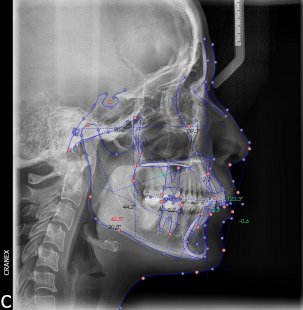

Inicio / Servicios / Análisis radiológico computarizado